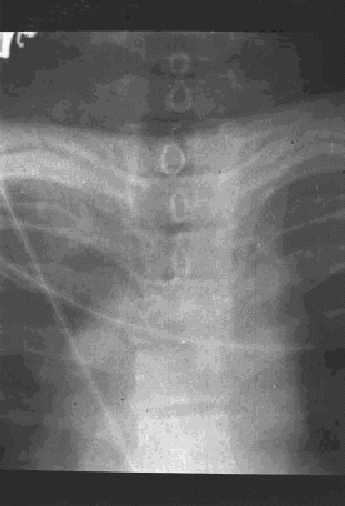

Figura 17.—Radiografía anteroposterior de tórax (portátil) realizada en la sala de críticos: Rarefacción de la mitad derecha del cuerpo vertebral. La línea de las apófisis espinosas se pierde no se visualiza a nivel de D4.